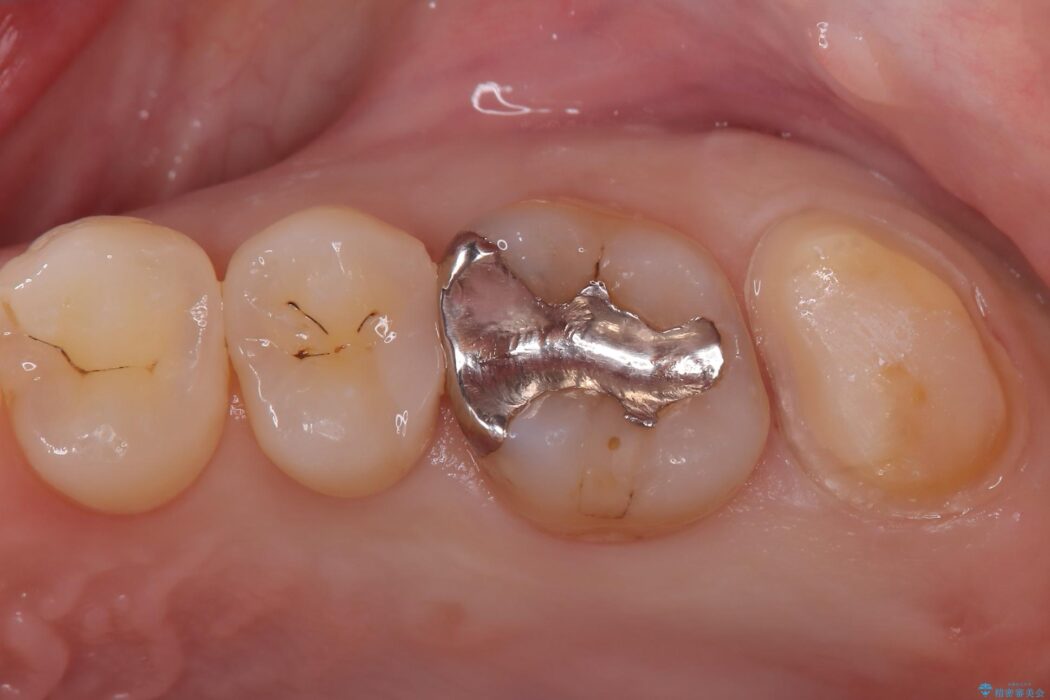

「冷たいものが強くしみる」とご相談にいらした患者様です。

精密検査の結果、非常に深い虫歯があり、通常であれば抜髄が必要な状態でした。

しかし、神経を抜くと歯の寿命が縮まってしまうため、今回は神経の一部を温存する部分的断髄法(VPT)を提案しました。